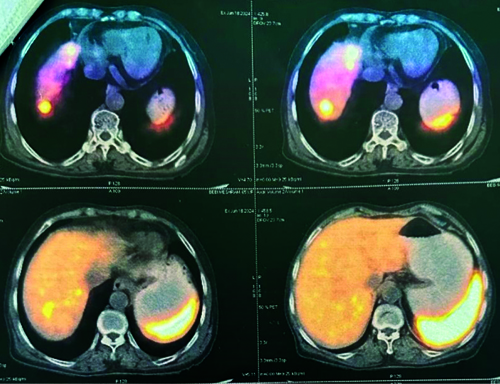

The patient was discharged and advised to follow-up with a Gallium-68 DOTATATE (DOTA) scan. The patient returned to the Surgical Outpatient Department (OPD) after two months with a DOTA scan report indicating a Somatostatin Receptor (SSTR) expressing lesion in a 4.4 centimetre segment of a small bowel loop, likely representing the primary mitotic lesion. Additionally, an SSTR receptor expressing lesion was observed in the right lobe of the liver, indicative of metastasis. No other SSTR expressing lesions were detected in the scanned areas of the body [Table/Fig-6,7]. Immunohistochemical markers were not carried out due to financial constraints. The patient was prescribed Imatinib 400 mg once a day for one month, along with a vitamin B12 supplement post-DOTA treatment.

DOTA-Positron Emission Tomography Computed Tomography (PET CT) scan report for assessment of tumour.

DOTA-PET CT scan report indicating a Somatostatin Receptor (SSTR) expressing lesion in a segment of a small bowel loop.